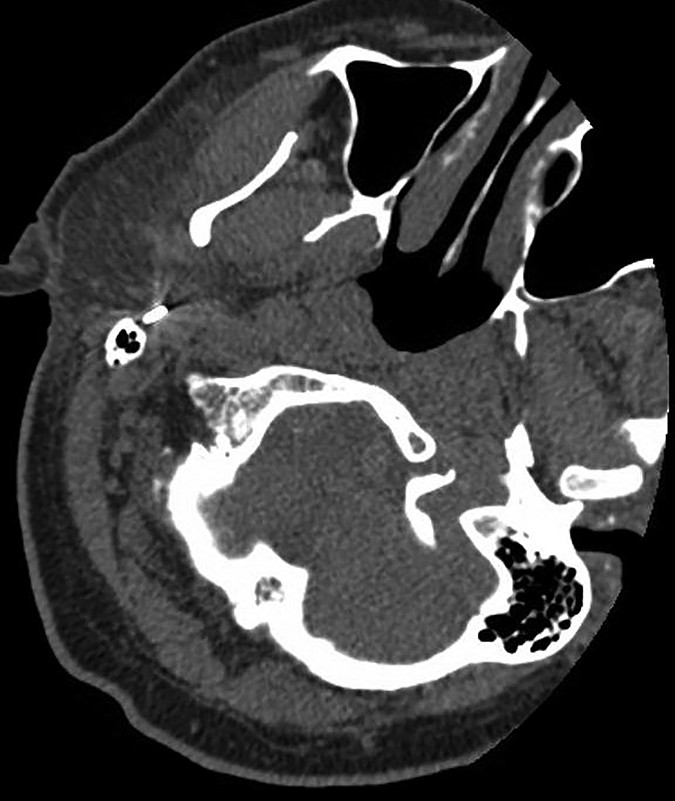

Speaking of studies, our illustrious Featured Sunday Session faculty are especially looking forward to leading breakout sessions regarding the various modalities most frequently found in imaging the suprahyoid neck. The comparative insensitivity of CT for artifacts, CT’s more comprehensive delineation of facial structures, and the promise of contrast-enhanced images to reveal critical vasculature continue to make CT more advantageous than ultrasound guidance (Fig. 2).

And because CT-guided fine-needle aspiration and biopsy can be performed with patients in three positions (supine, prone, lateral decubitus), multiple clinical studies in the imaging literature continue to conclude that this procedure remains safe and effective for obtaining tissue to diagnosis lesions of the head and neck. For quick reference, we encourage you to consult the following preprocedural patient care checklist for fine-needle aspiration and/or biopsy to help promote a professional and efficient imaging encounter with your patients: